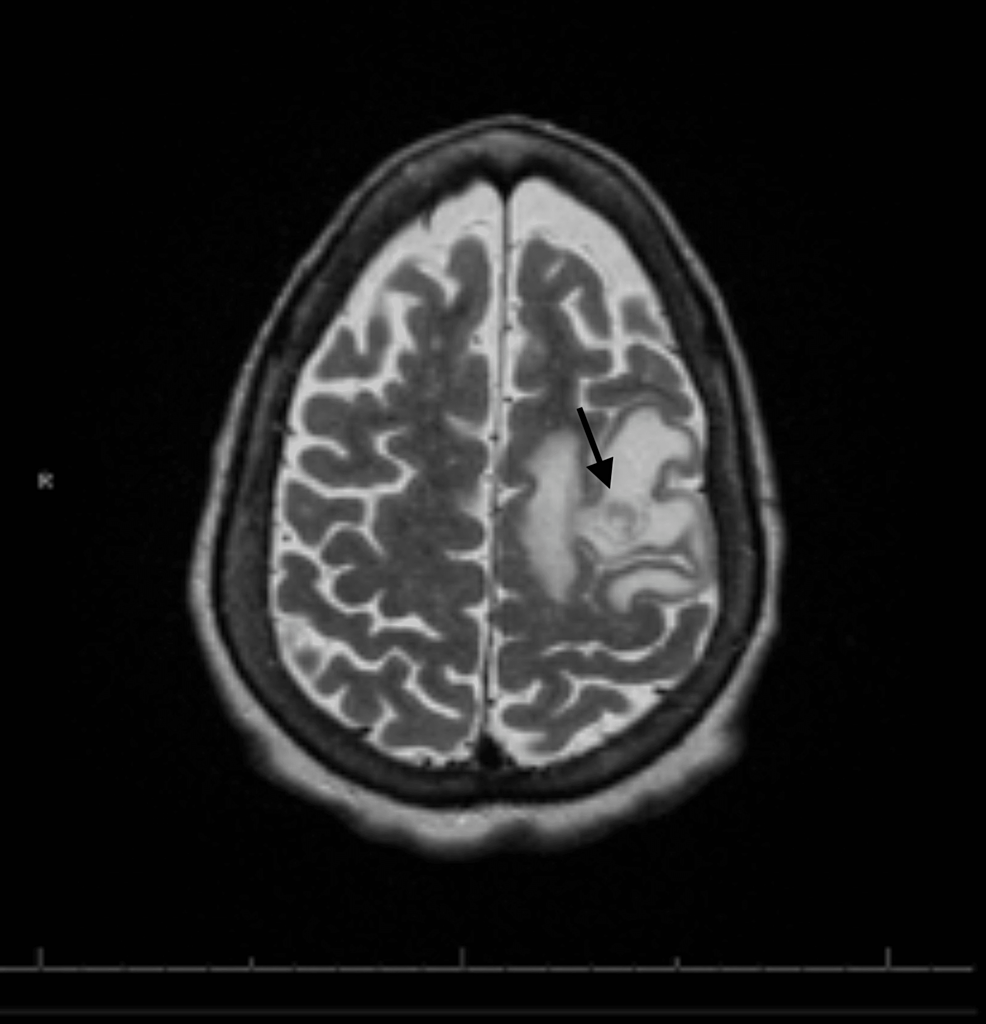

From www.researchgate.net

conventional Mri and 1 HMRS images of a typical glioblastoma. Notes... Download Scientific Alpha Beta Ratio Glioblastoma direct evidence that prostate tumors show high sensitivity to. in addition, we employed an α estimate of 0.26 gy −1 and an α/β ratio of 8 gy based. the analysis confirms a high value for the α/b ratio. The alpha/beta ratio for tumor. the alpha/beta ratio represents the dose, where cell killing from the linear and. Alpha Beta Ratio Glioblastoma.

From www.cureus.com

Cureus Glioblastoma Multiforme in a Patient With Alpha1Antitrypsin Deficiency Alpha Beta Ratio Glioblastoma The alpha/beta ratio for tumor. the selection of accurate lq parameters α, β and α/β is pivotal for a reliable estimate of radiation response. the alpha/beta ratio represents the dose, where cell killing from the linear and the quadratic components are equal. in addition, we employed an α estimate of 0.26 gy −1 and an α/β ratio. Alpha Beta Ratio Glioblastoma.